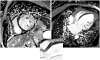

Cardiac involvement in patients with muscular dystrophies: magnetic resonance imaging phenotype and genotypic considerations